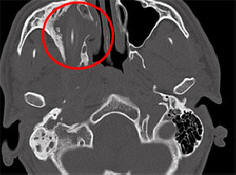

Některé nemoci a zranění jsou tak nenápadné člověk s nimi může žít roky bez podezření existence. Jako Američan, který trval téměř dva roky únik vlastní mozkové tekutiny pro výtok z nosu, německý občan podařilo se mu žít 15 let s tužkou v hlavě, hlásí Spiegel. Jak uvedli zástupci univerzitní nemocnice Cáchy, Severní Porýní-Vestfálsko, 24letá afghánská němčina původ jim přišel v roce 2011 o pomoc. Young osoba si stěžovala na přetrvávající bolesti hlavy, nachlazení a zhoršení vidění jedním okem. Lékaři dlouho nechápali, co se děje. neprovedl výpočetní tomografii. Ukázalo se to v mé hlavě pacient byl celou tu dobu tužkou 10 centimetrů. On je umístěné přímo nad pravým okem pro mladého muže a umístěné na něj tlak. Němec, který chtěl zůstat v anonymitě, to nedokázal vysvětlit odkud tužka přišla v jeho hlavě, ale později si vzpomněla jak neúspěšně padl v dětství. Lékaři odstranili cizí tělo z hlavy mladí muži, a on se brzy vzpamatoval. Teprve na konci května, po téměř roce po operaci se lékaři rozhodli věnovat tomuto případu samostatná konference, díky níž se o ní novináři dozvěděli. Toto není poprvé, co člověk dlouhodobě zvládl žít s cizím předmětem ve svém těle. Takže v roce 2007 starší německá žena trpící bolestmi hlavy a krvácení z nosu, odstranili tu tužku, která tam byla 50 let.